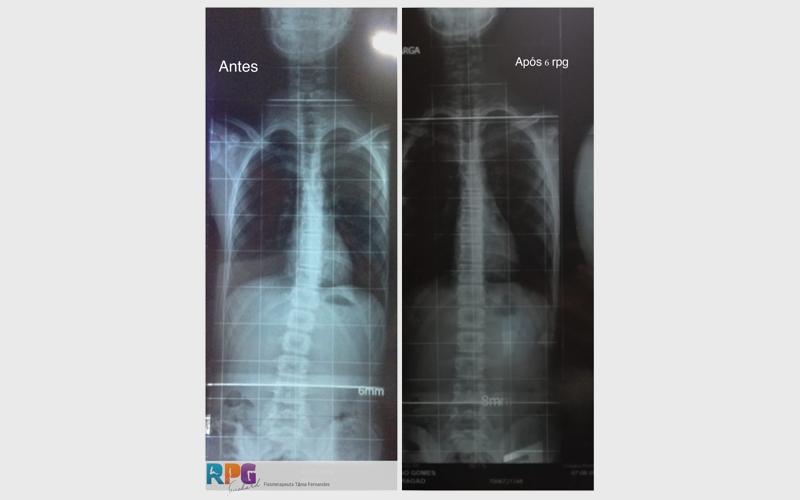

Existem tratamentos não cirúrgicos que podem atrasar a progressão ou até reduzir a Escoliose.